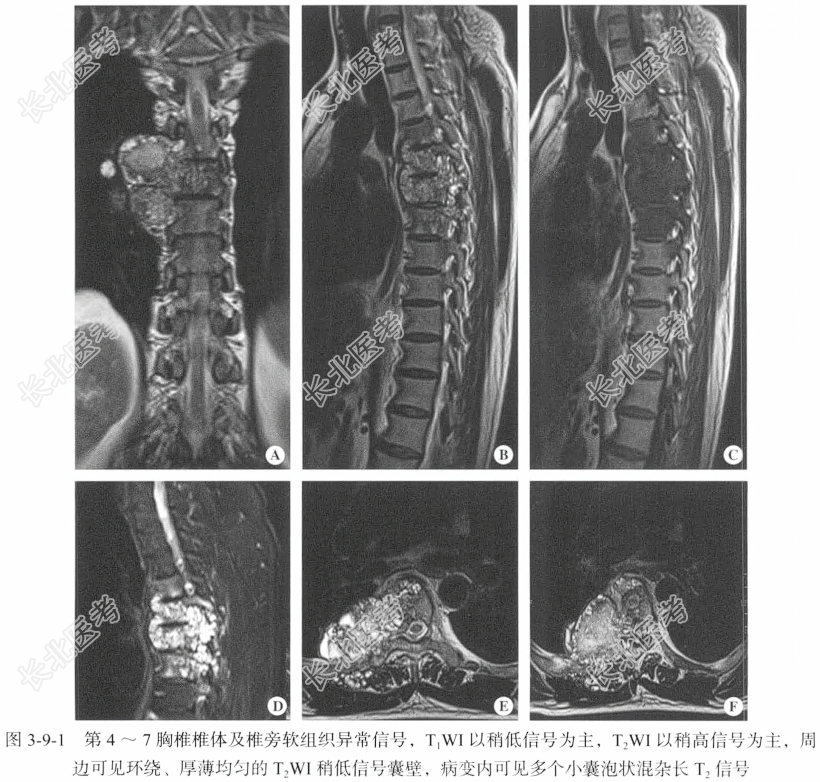

【影像图片】见图3-9-1。

【脊柱MRI检查】仰卧位,以矢状位扫描为主,扫描层厚为4mm,层间隔0.5mm,包括T₁WI、T₂WI及T₂WI脂肪抑制序列,扫描范围包括所需脊柱范围;辅以冠状位T₂WI,轴位T₂WI脂肪抑制序列,按需行增强检查,对比剂用量为0.2ml/kg。